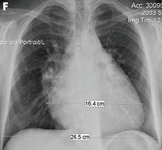

Chest x-ray in a patient with pulmonary regurgitation following repair of tetralogy of Fallot. The patient has a restrictive right ventricle and the heart is small

From: Chaturvedi RR, Redington AN. Heart. 2007 Jul;93(7):880-9; used with permission